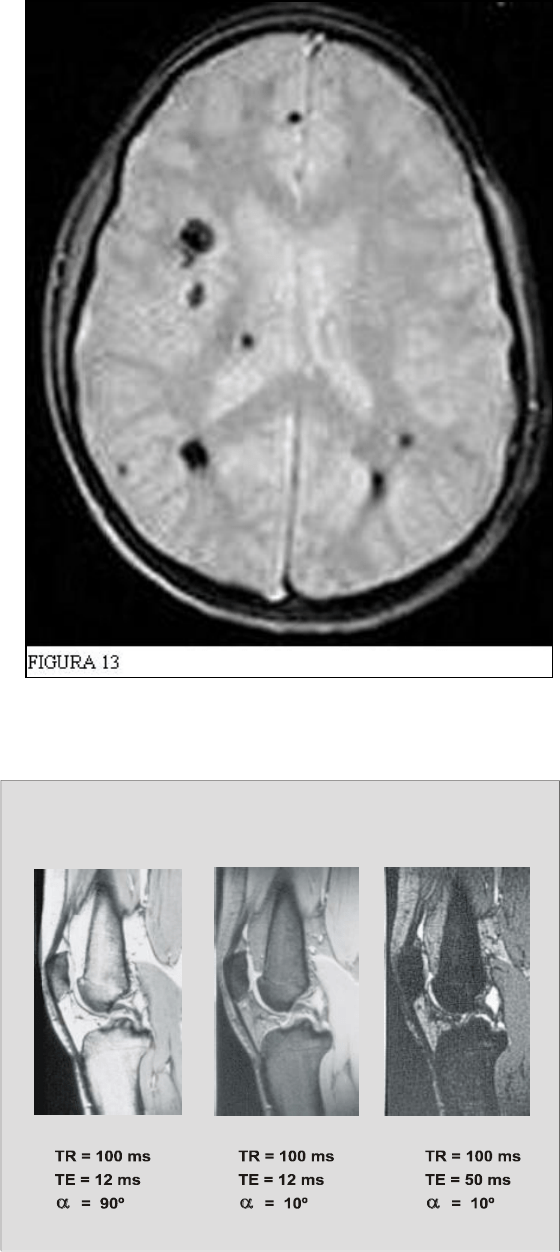

T2* es un tipo de contraste relacionado con el T2. La relajación transversal, o T2, es muy

de un contraste en T2 obtendremos un contraste similar, pero no igual, llamado T2*.

Este contraste suele obtenerse en secuencias GRE

3

, muy útiles en los estudios de cerebro

para evidenciar hemorragias, que se ven hipointensas. Las secuencias GRE también ponderan los

La figura 13 muestra un corte de cerebro, con hemorragias varias, en una secuencia GRE

ponderada en T2*.